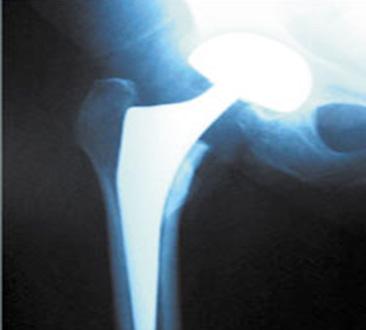

Manejo ortopédico de la artropatía hemofílica en México. Por: Dr. Armando R. Hernández Salgado, Ortopedista y Traumatólogo, Cirujano de Artroscopia y Cirugía de Rodilla, Especialista en Artropatía Hemofílica, Asesor Voluntario de FHRM. Pág. 109

Dr. Roberto Bernal, un ortopedista especializado en el tratamiento de los niños con Hemofilia. Por Redacción. Pág. 115